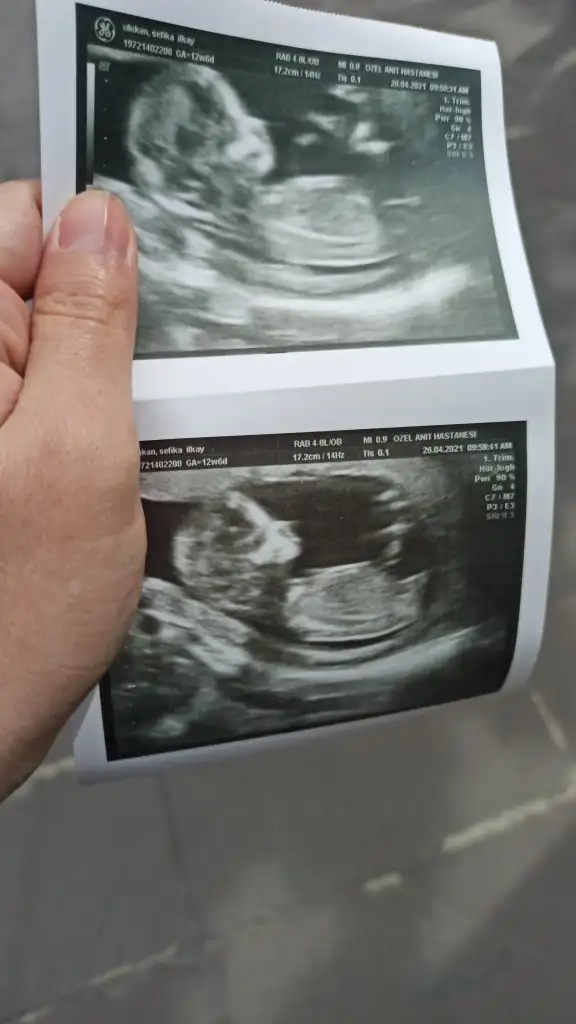

Merhaba arkadaşınız bana da yorum yapabilir mi

Eklentiler

• F4284577-1B65-4959-AAC9-ABAD3FBF87D1.webp

F4284577-1B65-4959-AAC9-ABAD3FBF87D1.webp

26,8 KB · Görüntüleme: 101

Oğlumun kese muz şeklindeydi.Bunda da kesesi aynı şekilde.Tek fark biri sağda biri solda.Ama bu kiz.Bende pek tutmadı.